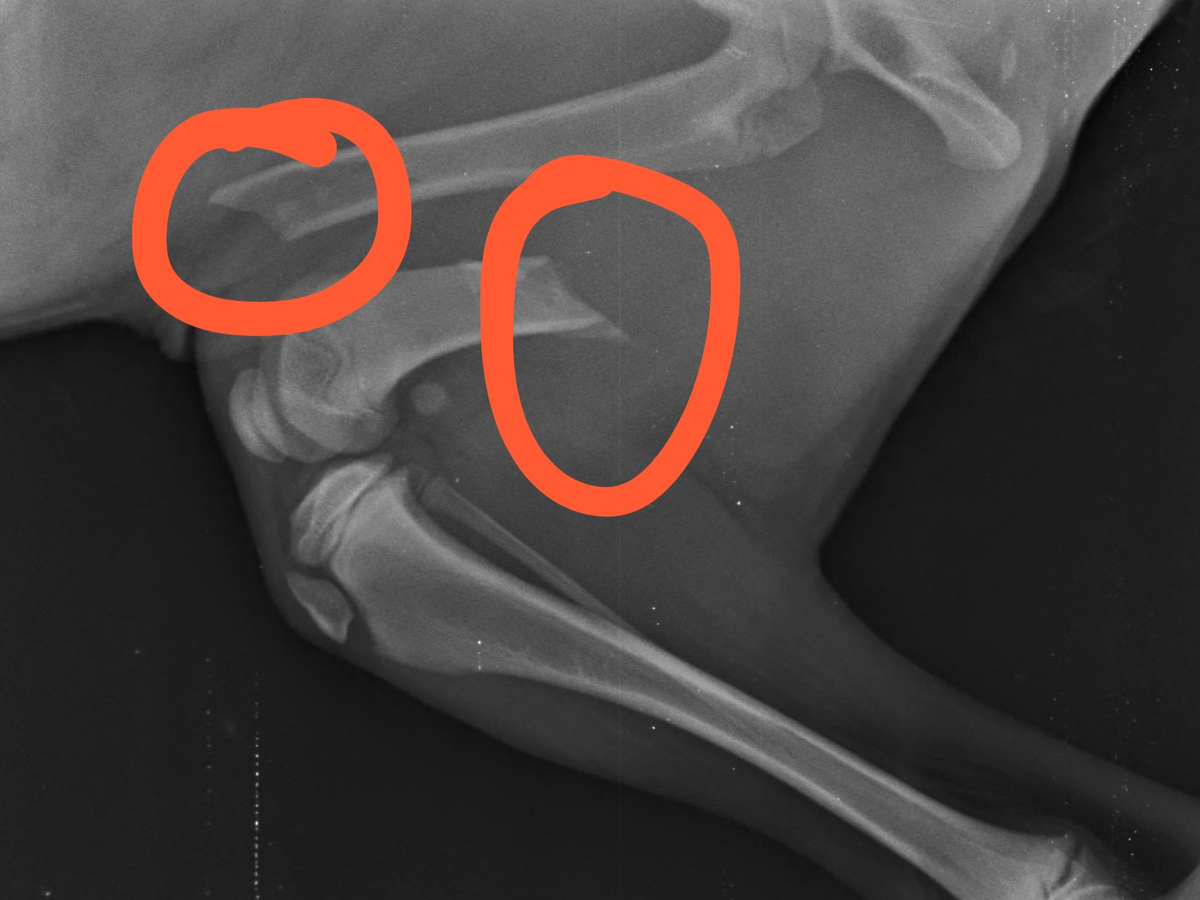

Hi I am Lisa and I am trying to raise funds to help pay for vet treatment for this puppy who was found on the side of the road with 2 broken legs. Poor little thing is a stray and needs our help.